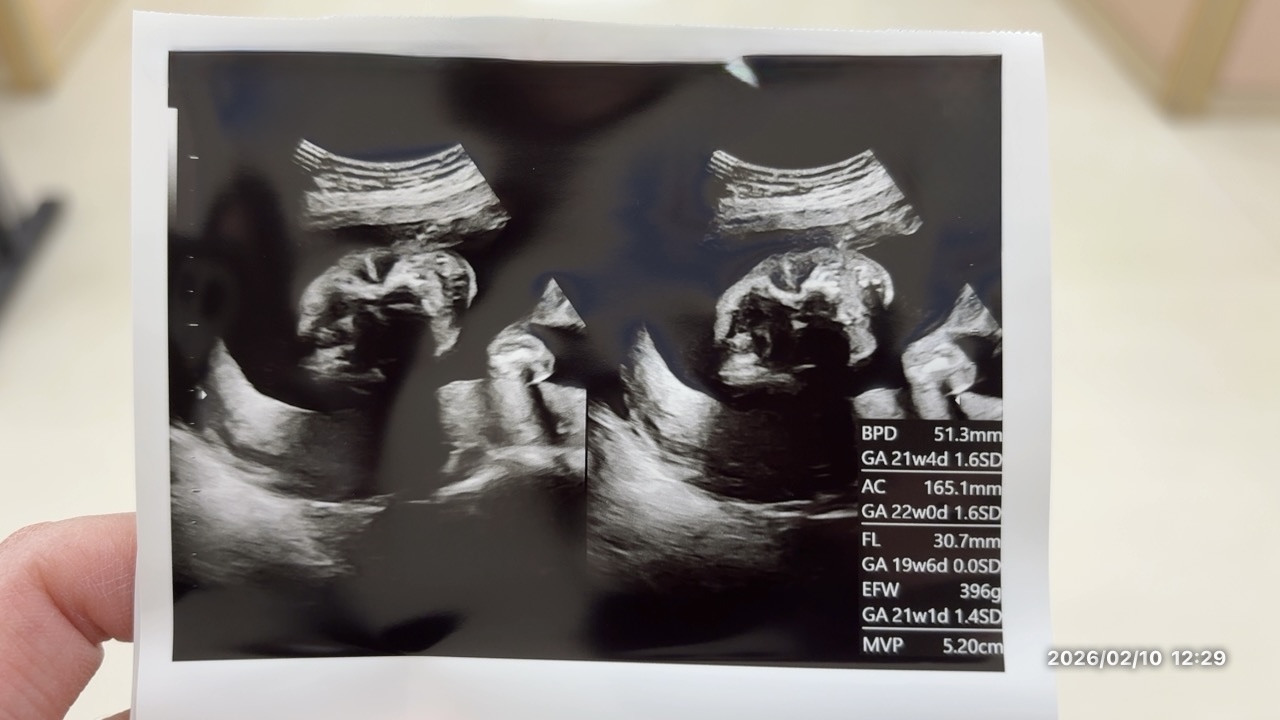

妊婦健診|20週胎児の写真と長女と長男の赤ちゃんの写真、赤ちゃんの性別、ママの雑談

今週で20週になった。

ベッドの上に横になって、お腹のまわりはかって、ジェル塗り塗りして見ていたら顔が見えた。

ちなみに、これはお尻の方からの写真。

足がちょっと上手くうつってなくて…わかりづらいっていう…私の弟からの話もあったけど👀

👤「はっきりしていて、私が特に言わなくてもわかると思います。😁」

👩「そうですね!🤣」

夜には家族にも話して、3人目は女の子推し組(パパとあいちゃん)は少ししょんぼりして、男の子推し組が(ママとけんちゃん👦)喜んだ。😁❤️